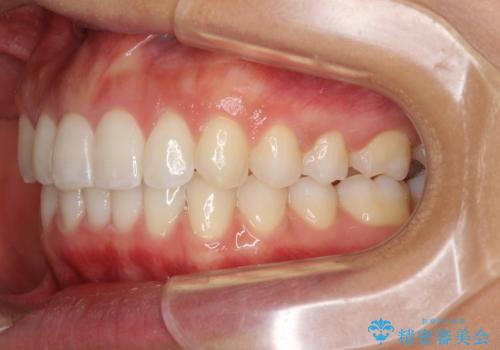

- 深い咬み合わせ(ディープバイト)と前歯のデコボコを気にして来院された患者様です。

インビザラインによる上下歯列の側方拡大と後方移動、IPR(歯と歯の間を削る)にるスペースの獲得により、デコボコとディープバイトを改善することとしました。

1日22時間の装着時間をしっかり守ってくださったので、予定通り1年で治療を終えることができました。

ディープバイトによる食いしばり癖も解消され、患者様には大変満足していただきました。